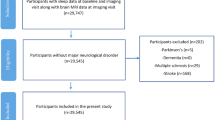

Subjects

Twenty-one patients with amnestic MCI (6 females, mean age: 69.8 ± 6.5 yr) and 21 cognitively healthy older (HO) subjects (10 females, mean age: 67 ± 5.5 yr) were enrolled in the study. Participants were primarily recruited from senior citizen’s associations, memory screening programs, and hospital dementia services. Informed consent was obtained from all participants, and the Ethical Committee for Human Research at the Pablo de Olavide University approved all procedures in accordance with the Declaration of Helsinki.

All participants received a neurological examination. Subjects diagnosed with amnestic MCI showed an idiopathic amnestic disorder with absence of impairment in cognitive areas other than memory, and all of them met core clinical criteria for MCI due to AD with an intermediate level of certainty. Elderly depression was excluded based on the short version of the Geriatric Depression Scale (scores ≤ 5). Inclusion criteria for HO subjects were normal cognitive performance relative to appropriate reference values for age and education, Clinical Dementia Rating (CDR) global score of 0 (no dementia), and normal independent function, judged both clinically and by means of an interview for deterioration in daily living activities. None of the participants were taking cholinesterase inhibitors and/or sedative-hypnotic drugs at the time of recruiting or during the study, nor did they report sleep-disordered breathing, movement disorders during sleep, or unusual sleep schedules (e.g., due to nocturnal shift work), as confirmed by bed partners and/or caregivers.